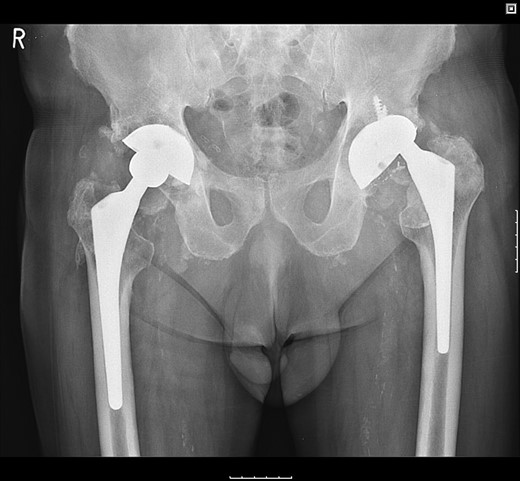

The femoral stem was kept firm in its proper position. Structural porous titanium acetabular augment (Regenerex™), reinforced with a cancellous allogeneic bone graft, was used to reconstruct the superior acetabular wall. The cup was completely revised using a Biomet® Regenerex Ringloc® multihole 56-mm acetabular cup and a Hi-wall Ringloc-x PE 54-mm liner. The previous 32-mm femoral head was replaced with a Bioball® 36-mm metal head and a Bioball® adapter standard (0 mm) Taper 11/13 (4° 3°), correcting the offset and achieving stability (Fig. 4).

A post-revision radiograph demonstrating a structural graft using the acetabular augment (Regenerex™) and revised cup in situ.